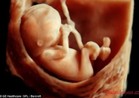

Uşaqlıqdan kənar hamiləlik mayalanmış yumurta hüceyrənin uşaqlıqda yox digər toxumalara implantasiya olunması deməkdir. Normada adın yumurta hüceyrəsi ilə kişi spermasının mayalanmasından sonra əmələ gələn hüceyrə "rüşeym"